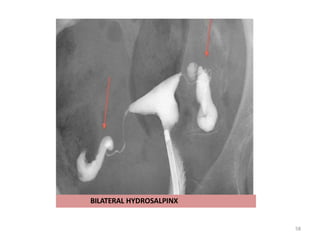

HYDROSALPINX

Bilateral distal fallopian tube block with fluid-filled dilatation of the tubes and

BILATERAL HYDROSALPINX